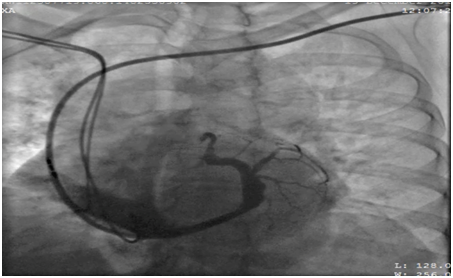

62 years old lady presented to the electrophysiology clinic with a history of shortness of breath, orthopnea, paroxysmal nocturnal dyspnea and lower limb swelling have started 3 weeks back. She denied any chest pain or syncope. She is known as HTN, IHD (S/P PCI to LAD 10 years ago), and History of Complete heart block (S/P DDDR pacemaker 6 years back). Previous LV function was normal (EF >55%, No significant valvular disease). On examination: She was conscious, oriented and vitally stable BP: 110/70 HR 70B/M, regular, RR: 22, Pso2: 96% on room air, T : 36.5, Congested neck vein observed, Chest: bilateral fine end in inspiratory basal crackles CVS: Normal S1, S2, no add sound or murmur Abdomen: Lax, soft, no masses Lower limb: Bilateral pitting edema ECG: well functioning paced rhythm; patient was diagnosed as new acute decompensate heart failure which was confirmed by ECHO showed: EF <35 %, with an impressive ventricular dyssynchrony, no significant valvular lesion, The patient was admitted in CCU as a case of ADHF (as a complication of RV pacing), was started on Ant failure treatment and the decision was taken to upgrade the DDDR TO CRTP. Then, Patient was driven in to Catha Lab. The procedure was initially attempted on the right, with successful cannulation of the right subclavian vein but unable to advance the guide wire to the superior vena cava (SVC), Venogram through the right anti-cubital vein showed a short occlusion of the right subclavian vein (Figure 1). The procedure was abandoned and LV lead implantation was performed on the left (Figure 2). Mild dissection of the coronary sinus occurred (Figure 3). Then sealed spontaneously and the LV lead was secured deeply in the posterolateral CS branch, a pair of long forceps were used for blunt dissection to create a subcutaneous tract from the right to the left. The proximal end of the LV lead was grasped with the forceps and tunneled above the sternum to rejoin the pocket (Figure 4). Then programming was done with good homeostasis.